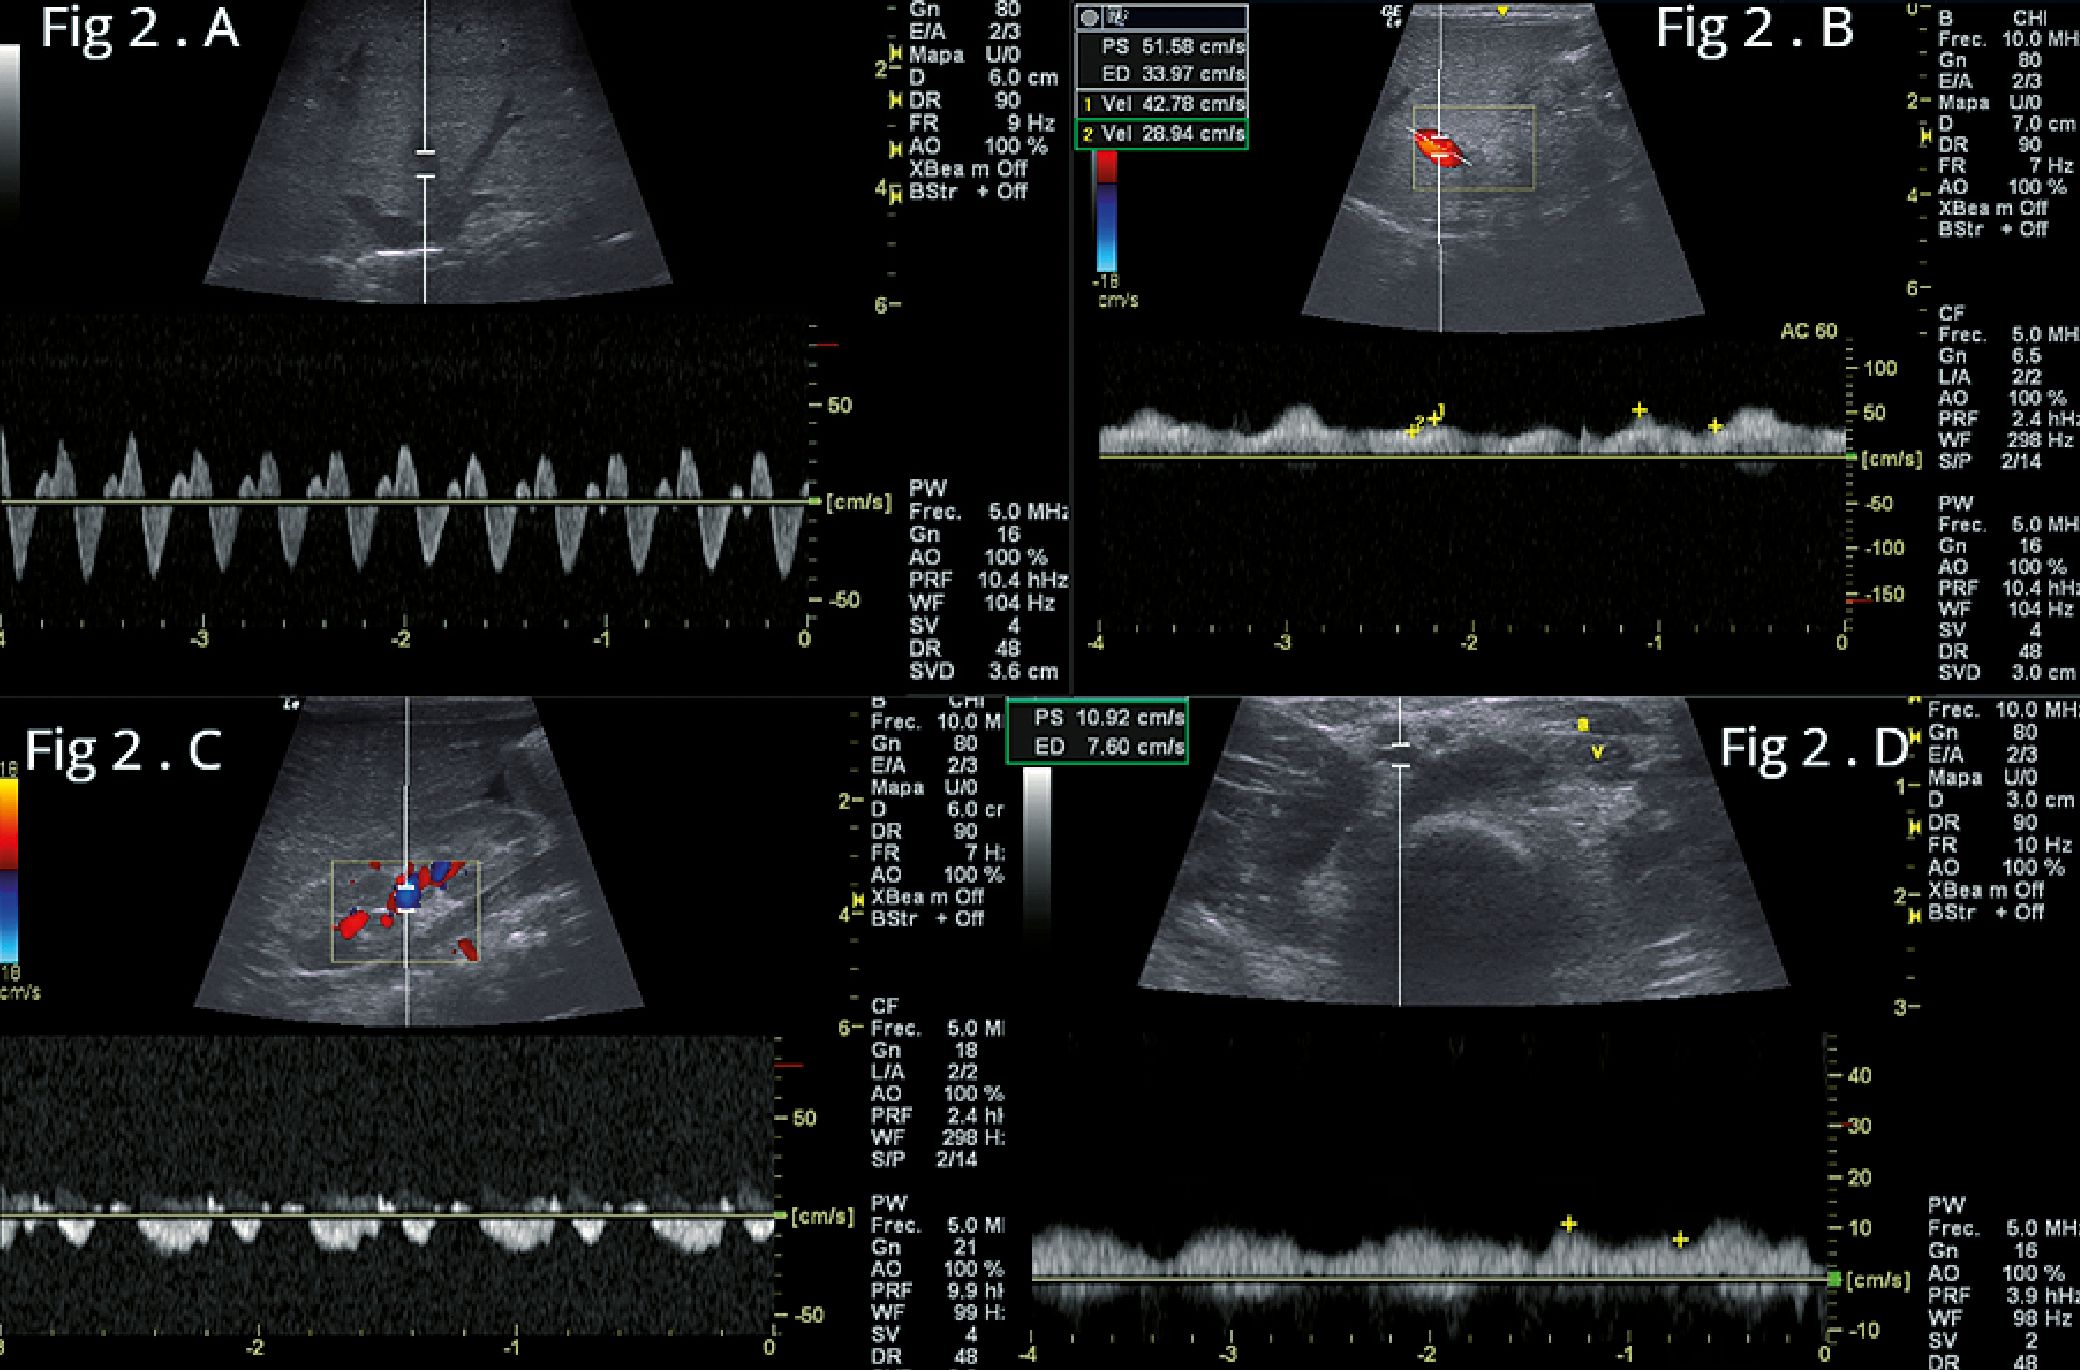

Utilizando un ecógrafo Logic Q con transductor sectorial, se realiza un ecocardiograma que muestra dilatación global de las cavidades con disfunción sistólica del ventrículo izquierdo (VI): Fracción de acortamiento del ventrículo izquierdo (FAVI) 25% y disfunción del ventrículo derecho (VD): con desplazamiento sistólico del plano del anillo tricúspideo (TAPSE, por sus siglas en ingles) en 7 mm e insuficiencia tricúspidea, se estimó la presión sistólica arterial pulmonar (PASP ): 60 mmHg, con estos hallazgos, se indicó adrenalina: 0,1 mcg/kg/m (mcg/kg/m), milrino- na: 0,3 mcg/kg/m2 y sildenafil. Se suspende la dopamina. Con transductor lineal se evaluaron los vasos abdominales desde la vista subcostal, mostrando un diámetro del eje corto de la vena cava inferior (VCI): 8 mm (sin colapso) con relación a la aorta abdominal: 4 mm, en el análisis de las venas suprahepática, porta y renal. se calcula una puntuación VExUS: 2 (Figura 2 A- B-C). Se realizó evaluación doppler de la vena femoral común (VFC) izquierda, observándose alteración de su patrón normal (Figura 2D)

Figuras 2. Flujos venosos antes de iniciar el tratamiento. A: flujo de vena suprahepática, presencia de onda D mayor qué onda S y onda A retrógrada; B: flujo de la vena porta, flujo pulsátil con índice de pulsatilidad (IP) > 30%. (VExUS 2); C: Flujo de vena y arteria renal, flujo bifásico sistodiastólico (VExUS 2), índice de resistencia renal (IRR): 0,82; D: vena femoral común izquierda, onda pulsátil bifásica.

En el análisis de los vasos abdominales de nuestro paciente se evidencia, En primer lugar, su Doppler de vena hepática mostró D onda S más larga (Figura 2A), su Doppler de vena porta mostró un índice de pulsatilidad superior al 30% (Figura 2B) y su Doppler venoso intrarrenal mostró un patrón de flujo bifásico (sistólico-diastólico) (Figura 2C). Los tres hallazgos de Doppler, en conjunto, argumentan fuertemente a favor de un estado congestivo venoso moderado (al menos de 2 de 3 sistemas venosos con congestión moderada producen una puntuación VExUS de 2).

La base de la insonación de la vena femoral común (VFC) radica en establecer si la insuficiencia del ventrículo derecho afecta también a los territorios venosos distales[5]. Nuestro paciente presentó disfunción biventricular con hipertensión pulmonar moderada y compromiso moderado del flujo venoso abdominal, (VExUS puntuación 2).